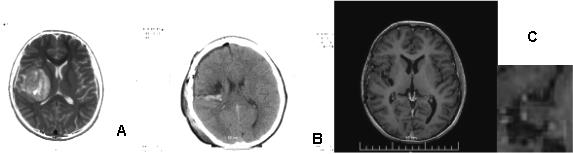

A 17-year-old boy with extremely rare primary brain neuroblastoma/supratentorial primitive neuroectodermal tumor (PNET) in the right temporo-parietal region is presented. Complex treatment, including subtotal surgery, conventional fractionated craniospinal radiotherapy (CSRT) with DD 1.8 Gy up to TD 30 Gy with boost RT in the tumor bed up to TD 56 Gy with DD 1.8 Gy and 6 courses of adjuvant Ch (Etoposide and Carboplatin) was conducted (Figure 10). After 2 years of control MRI, a local recurrence was established (Figure 11), in which an additional local RT with DD 2Gy to TD 34Gy was performed. After 7 months of complementary local RT, MRI demonstrated local tumor control (Figure 12). After three months of MRI, a second local recurrence was diagnosed, which was operated on (Figure 13/А). Postoperative bone marrow transplantation of stem cells was performed, but 1 year later a third local recurrence was diagnosed (Figure 13/В).

The third recurrence was operated. Histological result: Brain tissue with infiltration from nests and derived from small atypical cells with hyperchromic nuclei and visible nucleoli. Tumor cells form pseudosockets. Focal hemorrhages and necrosis are seen- Histological data for neuroblastoma. Given the previous peripheral stem cell transplantation and the high risk of hematological toxicity, 6 courses of Ch with Vincristine and Temodal in a reduced dose were administrated. MRI 2 months after the completion of Ch visualized a fourth local recurrence and the patient was referred to radiosurgery with a gamma knife in Turkey where a single TD 14 Gy has been performed. Paresis of the left limbs suddenly occurred 2 months after the procedure. On contrast-enhanced MRI with evidence of subacute hematoma in the postoperative porencephalic cyst in the right temporoparietal brain area (Figure 14/А). СT in 20 days reported a persistent subacute hematoma in the right temporoparietal postoperative porencephalic cyst (Figure 14/ B).

Figure 10: MRI of primary brain neuroblastoma: A / Preoperative; C / Postoperative; C / Local tumor control after complex treatment / subtotal surgery, CSRT with boost RT in the tumor bed up to 56 Gy and 6 cycles of chemotherapy according to the BEP protocol.

In the fourth clinical case, the young boy with the rare diagnosis of brain neuroblastoma (PNET) concerns extremely malignant neoplasm. Complex treatment, including subtotal surgery, conventional fractionated craniospinal radiotherapy (CSRT) with DD 1.8 Gy up to TD 30 Gy with boost RT in the tumor bed up to TD 56 Gy with DD 1.8 Gy and 6 courses of adjuvant Ch (Etoposide and Carboplatin) was applied (Figure 10). After 2 years of control MRI, a local recurrence was established (Figure 11), in which an additional local RT with DD 2Gy to TD 34Gy was performed. The prognosis and survival directly depend on the volume of the surgery, the magnitude of the postoperative brain residue (>1.5 cm2), the infiltration of the IV ventricle and the pathohistological cell variant [69,70]. Subtotal surgical resection and evidence of disease dissemination are considered poor prognostic factors [71]. In adult patients, the five-year progression-free survival rate ranges from 45% to 78% depending on the risk class [72-74]. In the young patient with a primary brain PNET, the bone marrow transplantation with stem cells was conducted, 1 year after which we diagnosed third local recurrence (Figure 13). For a period of 5 years, despite complex treatment, including subtotal surgery, conventional fractionated CSRT with boost, Ch, local RT and bone marrow transplantation, 2 months after the completion of Ch on MRI, a fourth local recurrence occurred, subjected to radiosurgery with a gamma knife in Turkey with a single fraction 14 Gy. After 2 months from SRS, contrast-enhanced MRT reported evidence of late subacute hematoma in the postoperative porencephalic cyst in the right temporoparietal brain area (Figure 14/А). СT in 20 days reported a persistent subacute hematoma in the right temporoparietal postoperative porencephalic cyst (Figure 14/B).